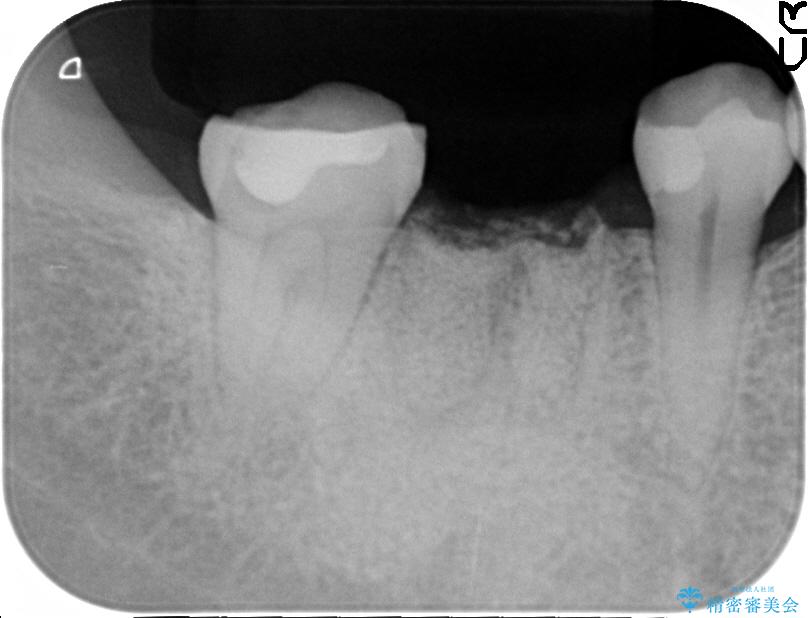

抜歯を行った当日に骨の維持をする為、人工の骨を充填しました。インプラントを埋入する際には、ほとんどが自分の骨に置き換わっており、頬舌的なへこみを引き起こす事もなく、審美性・機能性ともに維持する事が出来ました。

また今回の治療では「バイコンインプラント」を使用する事により、インプラントの土台とセラミッククラウンを付ける際にセメントが全く残らないという利点を生かしたところ、見た目にも綺麗に仕上がり、患者様にも喜んでいただきました。